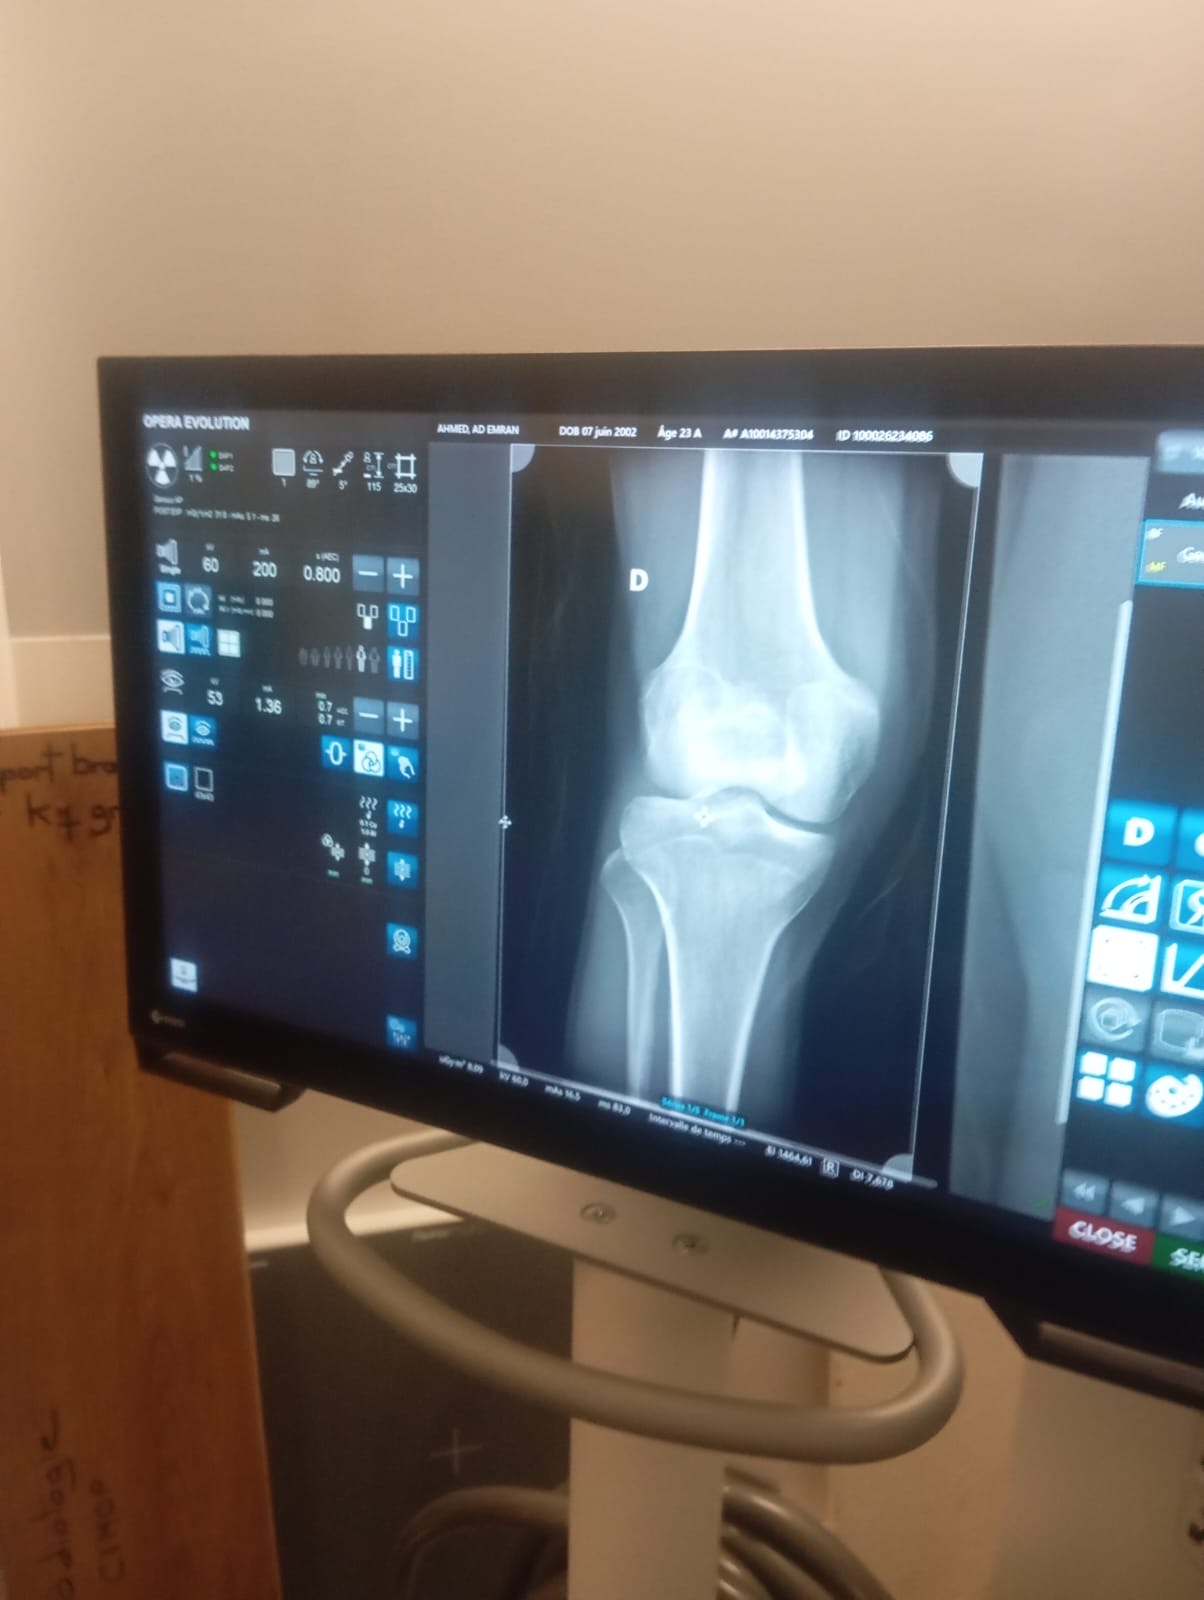

তাৎক্ষণিকভাবে পুলিশ ও দমকল বাহিনী (Pompiers) ঘটনাস্থলে এসে তাকে প্রাথমিক চিকিৎসা দিয়ে দ্রুত হাসপাতালে নিয়ে যায়। হাসপাতালে নেওয়ার পর এক্স-রে ও অন্যান্য মেডিকেল চেকআপের মাধ্যমে নিশ্চিত হওয়া হয়, তার শরীরের কোথাও বড় ধরনের হাড় ভাঙা বা অভ্যন্তরীণ জখম হয়নি। প্রয়োজনীয় চিকিৎসা শেষে চিকিৎসকরা তাকে কিছুদিন সম্পূর্ণ বিশ্রামে থাকার পরামর্শ দিয়ে রিলিজ দেন।